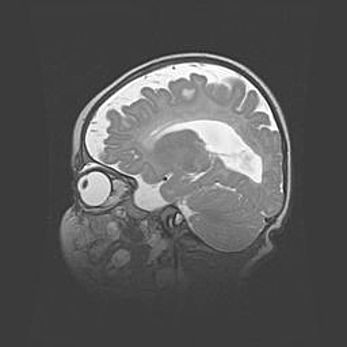

Церебральная ишемия II.

Возраст: 5 дней

Вес: 3400 г

Пол: женский

Окружность головы: 35 см

Срок гестации: 39 недель

Церебральная ишемия – это заболевание, характеризующееся недостаточностью (гипоксией) либо полным прекращением (аноксией) снабжения мозга кислородом по причине закупорки одного или нескольких сосудов. Это приводит к  что метаболическим расстройствам различной степени тяжести в тканях головного мозга, развитию коагуляционных некрозов и гибели нейронов.